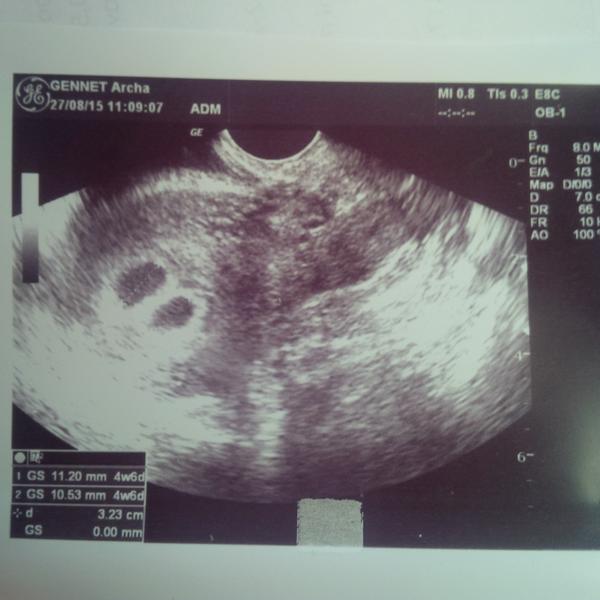

Tak výsledky už mám hcg 32642 🙂 🙂 🙂

Gratuluji, to je obrovská hodnota, to budou určitě dvojčátka!!! 😀

Hele vypadá to na dvojčátka 😉